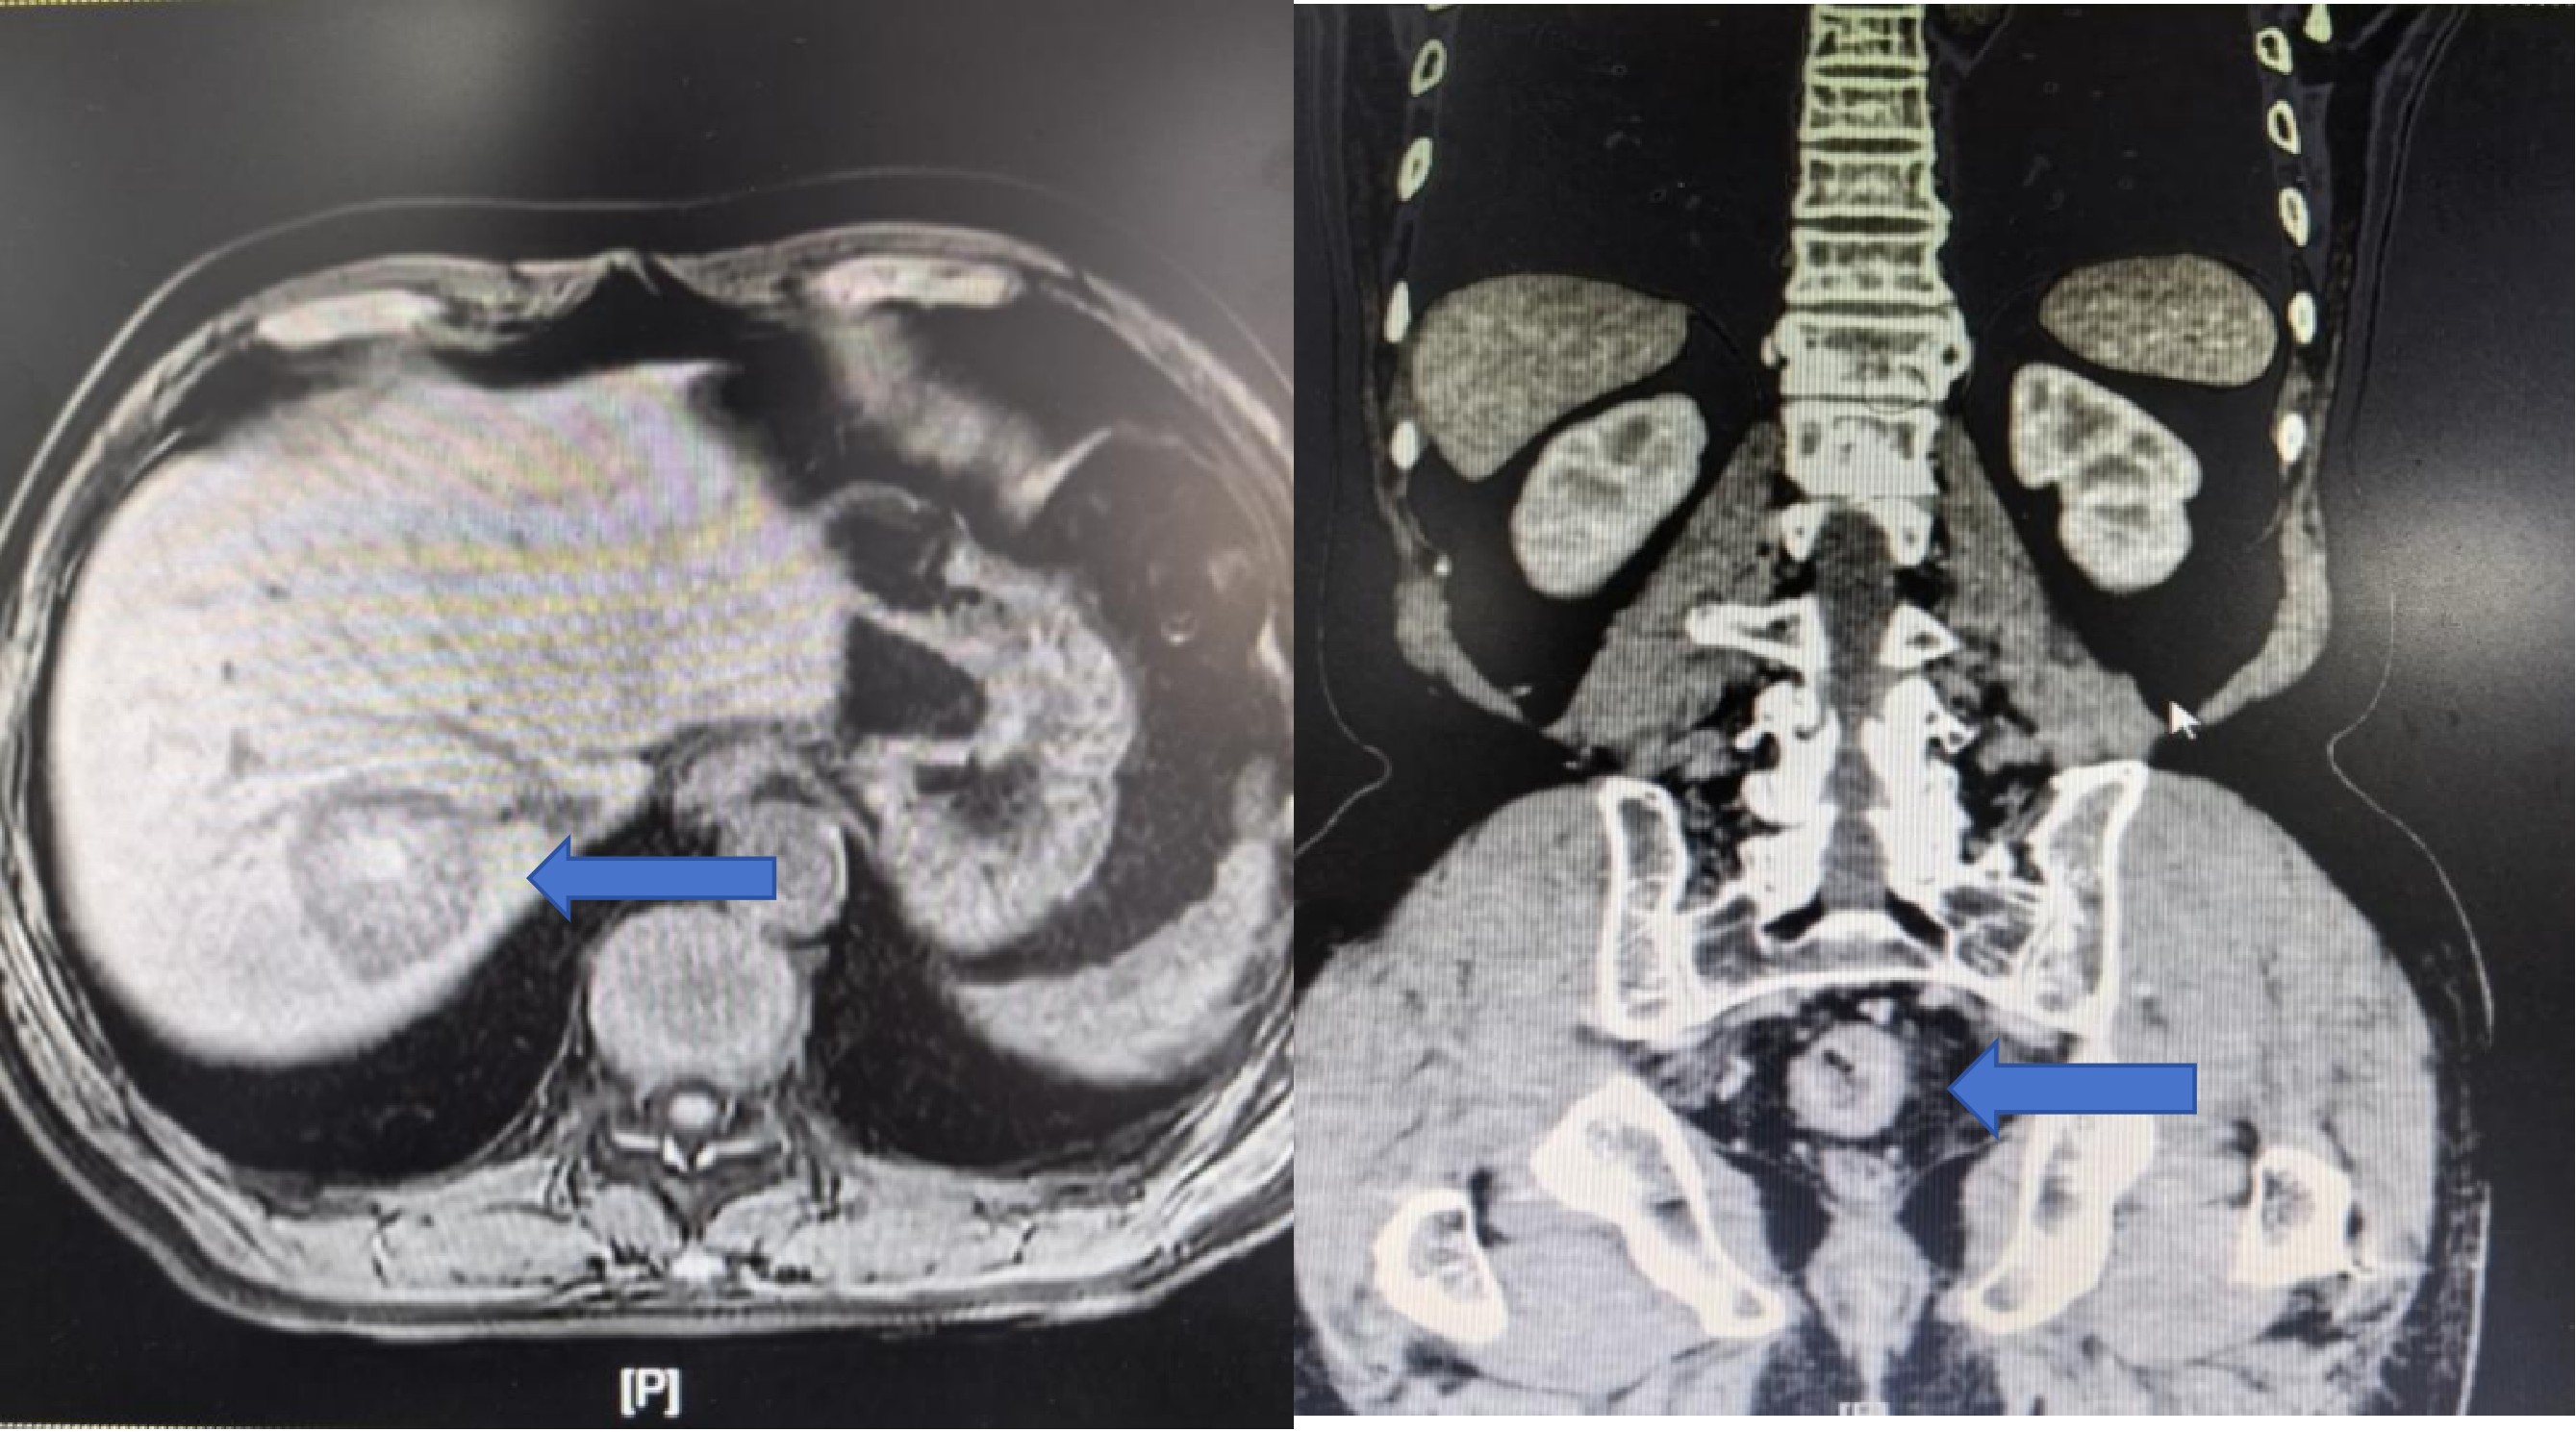

2025年11月,该患者因“大便习惯改变持续4月余”前来湘雅三医院就诊。门诊肠镜检查高度怀疑直肠癌,随后的肿块活检病理结果确诊为直肠腺癌。患者被收入胃肠外科二病区朱晒红/朱利勇教授团队。入院后,详尽的术前检查揭示了更为复杂的病情:腹部CT提示肝右叶存在异常高密度灶,高度怀疑为转移瘤并伴出血。肝脏MRI进一步明确了诊断:肝右后叶上段占位,考虑转移瘤并出血等。术前诊断清晰——直肠腺癌合并肝转移。面对这一直肠腺癌合并肝转移的复杂病例,是同时针对同期切除原发病灶与转移灶,还是先实施辅助治疗这一关键诊疗决策,朱利勇教授团队第一时间联合肝胆外科、肿瘤科、麻醉科、临床营养科等多学科专家开展MDT会诊。经过充分讨论与全面评估,专家团队一致认为,同期切除直肠原发病灶和肝脏转移病灶是当前对患者最有利的治疗策略,术后将根据病理结果辅以化疗等综合治疗。